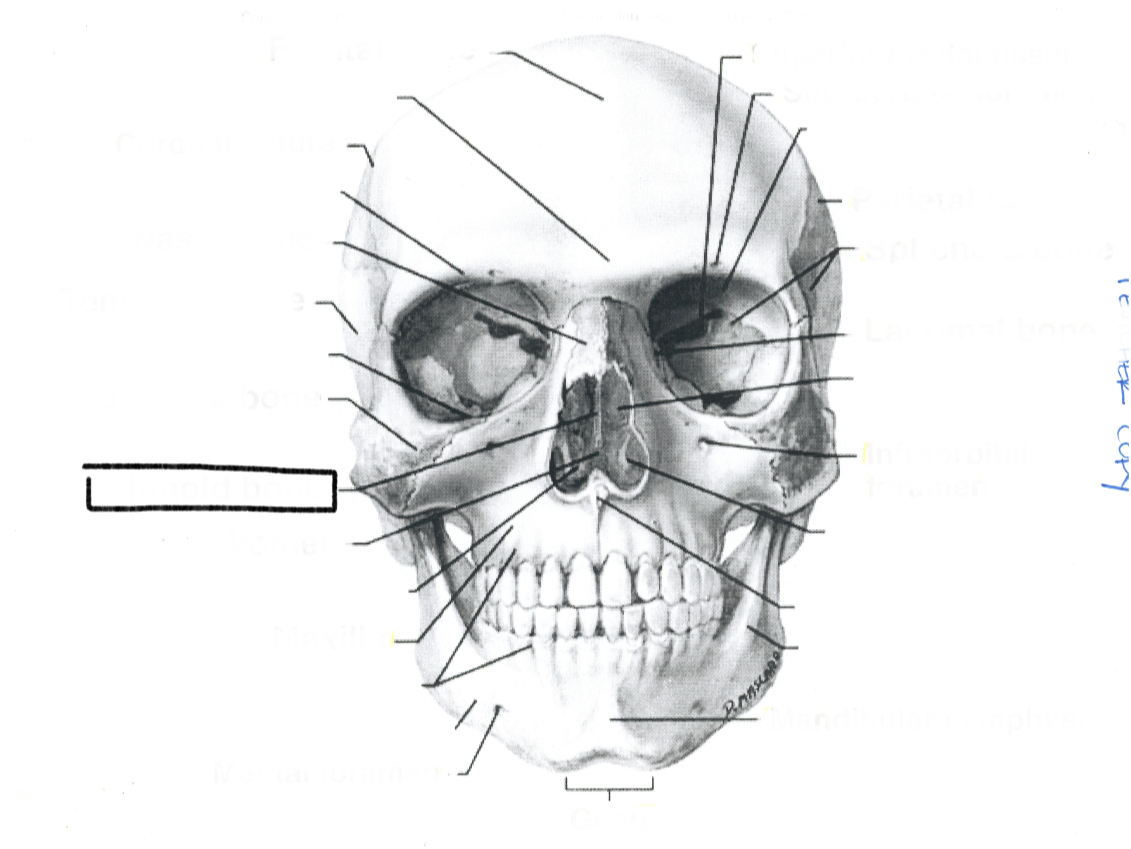

What is this?

Lacrimal bone

What is this?

Sphenoid bone

What is this?

Parietal bone

What is this?

Infraorbital foremen

What is this?

Supraorbital foramen

What is this?

Superior orbital fissure

What is this?

Mandibular symphysis

What is this?

Genu

What is this?

Mental foramen

What is this?

Maxilla

What is this?

Ethmoid bone

What is this?

Zygomatic bone

What is this?

Temporal bone

What is this?

Nasal bone

What is this?

Coronal suture

What is this?

Frontal bone